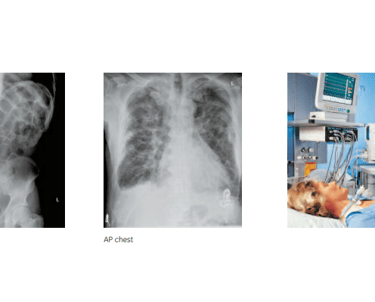

Intensive Care Units (ICU):

The mobile X-ray system is ideal for ICU settings, where bedridden patients need to be imaged without the need to transport them to traditional X-ray rooms. The easy maneuverability and battery-powered operation make it perfect for imaging in critical care environments.